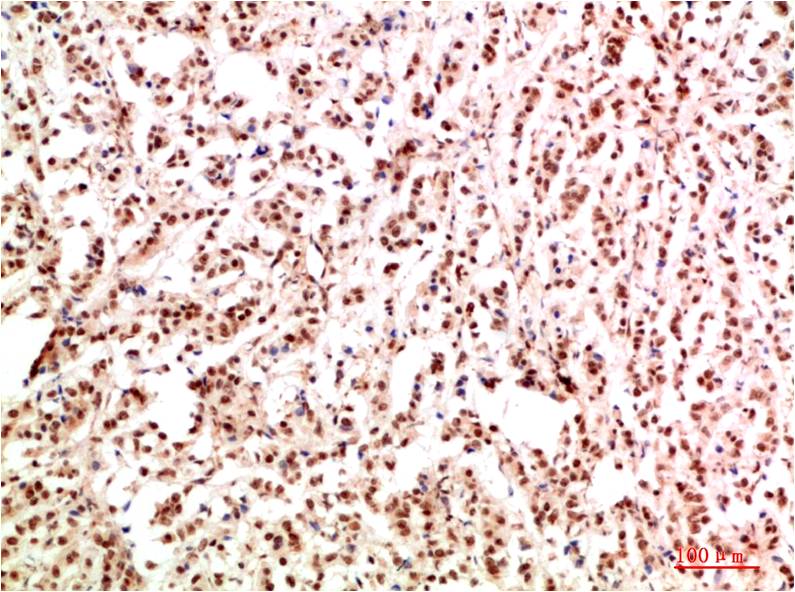

Acetyl P53(K382) Mouse Monoclonal Antibody(5H10)

Applications :IHC

| Recommended dilutions: | IHC: 1:100-200 |

| Specificity: | The Acetyl P53(K382) Mouse Monoclonal Antibody can detects endogenous Acetyl P53(K382) proteins. |